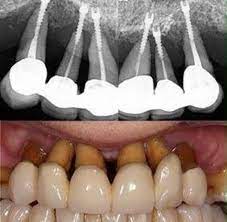

In this case the only option is to have a root canal followed by placement of a crown. In very rare situations the loss of a filling or fractured tooth may be so severe that the only option is extraction. The root canal filling or a tooth filling is a process to fill your decayed tooth with an amalgam of several materials to cure the tooth sensitivity.

If your recent root canal filling or packing falls out you may feel the same tooth sensitivity or a severe tooth pain again. There may be some other symptoms that suddenly arise after your root canal. Trauma to the tooth or root.

I have made an appointment with the dentist tomorrow but I am really worried. What Makes a Filling Fall Out Potential Causes. Dental fillings need to be replaced every 5 to 30 years.